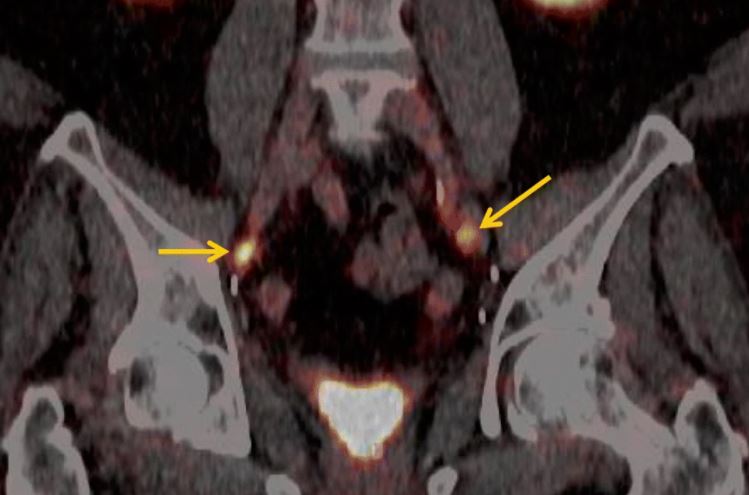

Áttörést hozhat a Pozitron-Diagnosztika Központ több százmillió forintos fejlesztése a prosztatarákkal diagnosztizáltak életében; az innovatív magyar egészségügyi cég által kifejlesztett nyomjelző anyag ugyanis a betegeknél az áttéteket minden eddigi módszernél pontosabban mutatja ki – ismertette Szakáll Szabolcs nukleáris medicina szakorvos, a Pozitron-Diagnosztika Központ orvos igazgatója az MTI-nek.

Az orvos igazgató elmondta, hogy a cég által kifejlesztett, speciális nyomjelzőt a központ saját laboratóriumában, saját részecskegyorsítójával állítja elő. Az egészségügyi fejlesztés révén a régióban elsőként Magyarországon nyílt lehetőség a nagy pontosságú PSMA-specifikus nyomjelző anyag alkalmazására a prosztatadaganatos betegek kivizsgálásában.

Szakáll Szabolcs felhívta a figyelmet arra, hogy a statisztikák szerint a prosztatarák Magyarországon a férfiak második leggyakrabban diagnosztizált daganata, mely az ötödik vezető halálok, az öregedő európai társadalmakra általában jellemzően. Évente 5-6000 új prosztatarákos megbetegedést diagnosztizálnak, a radikális műtéten átesettek egyharmadánál azonban a sebészi- vagy sugárterápiát követően kiújul a betegség, a fel nem fedezett áttétek miatt. A PSMA PET/CT-vizsgálatok elsődleges célja az ilyen kiújulások felderítése, kimutatása.